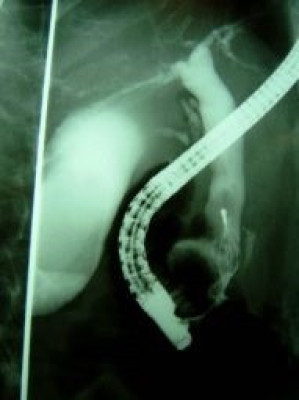

Colelitiasis y coledocolitiasis ERCP

Envíado por Dr. Carlos Miguel Zavaleta Consuegra